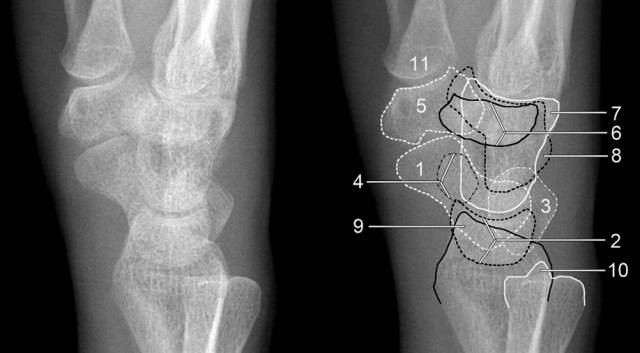

1、腕关节X线下的正常形态

( 1)正位片上:前后排腕骨后缘形成光滑的弧线;前后排腕骨不重叠;头、钩、月、三角骨间形成十字间隙。月骨于正位片上为楔形、侧位片上为月牙形,窝状关节面朝前、且与头状骨紧贴。

1.舟骨 2.月骨 3.三角骨 4.豆状骨 5.大多角骨 6.小多角骨 7.头状骨 8.钩骨 9.桡骨茎突 10.尺骨茎突 11.第一掌骨基部

(2)侧位片上:桡骨纵轴通过月骨和头骨;前排腕骨自下而上分别为大、小、头、钩骨,后排自下而上为舟、月(豆)、三角骨。